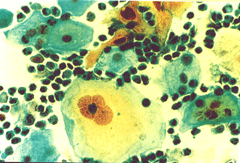

Περιστατικό ασθενούς που παρακολουθείται στο ιατρείο μας από το 1993, τότε ηλικίας 37 ετών, αρχικά λόγω ασυμπατωματικού κυτταρολογικά εμμένοντας έρπητος τραχήλου της μήτρας. Το γεγονός αυτό μας οδήγησε στην διερεύνηση της περιπτώσεως. Η ασθενής επασχε από A.I.D.S.

Είχαμε την ευκαρία να παρακολουθήσουμε ανά 6μηνο γυναικολογικά, κολποσκοιπικά και κυτταρολογικά την γυναίκα από το 1993 μεχρι και το 2008. Από τις εξετασεις αυτές, παρουσιάζουμε χαρακτηριστικές κυτταρολογικές εικόνες . Όι παρακάτω κυτταρολογικές εικονες προέρχονται από την 2η κατά σειρά εξέταση της ασθενούς το 1993. Οι κυτταρολογικές αλλοιώσεις ερπητος συνεχίζουν να υφίστανται.

Ταση γιγαντιοκυττάρωσης όλων των επιθηλιακώ στοιβάδων, κοιλοκυττάρωση, διογκωμένοι υπερχρωματικοί και ανισομεγέθεις πυρήνες , με διάλυση δομής χρωματίνης, συχνά διογκωμενοι πυρήνες με εικόνα φαινομένου ΄΄θολού γυαλιού΄΄